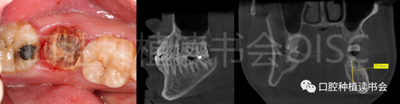

圖1 無法保留的上頜隱裂后牙,拔牙后即刻種植。

患者為70歲女性,右下后牙樁核冠因遠(yuǎn)中牙根縱裂脫落,全身健康狀況良好,輕度骨質(zhì)疏松??趦?nèi)檢查:47殘根,遠(yuǎn)中根縱裂,部分根面已腐至齦下2mm,叩(++),松(-);48近中傾斜阻生,咬合關(guān)系、修復(fù)間隙及牙周情況正常(圖12)。

圖12 遠(yuǎn)中根縱裂及根面齲導(dǎo)致47殘根無法保留。

術(shù)前CBCT(美亞光電)檢查:47根分叉下方骨高度及骨寬度滿足即刻種植要求(圖13)。

圖13 47根分叉區(qū)骨寬度及骨高度(與下頜神經(jīng)管之間的距離)滿足即刻種植要求。